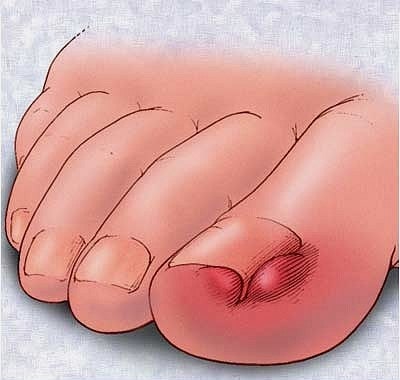

관통 발톱이 발생할 때, 큰 발가락이 빨간색으로 변하며 부풀어진다.이 주에서는 지속적인 마찰, 조직 성장, 조직 성장을 유발한다.극단적인 고통 때문에 보통 걷는 것이 어려운 경우에 따라 걷잡을 수 없다.자세한 내용은 그들을 절단하는 습관이다.발가락에 과도한 압력을 적용하지 않지만, 단순히 잘라내는 습관이 될 수 있지만, 단순히 잘라내는 습관이 될 수 있다.타원형의 모양을 잘라내면, 발톱은 수직적으로 자랄 수 있는 것보다 옆으로 자랄 수 있습니다.이것은 염증을 유발한다.이것은 마치 이런 것 같은 손톱이 좋아하는 손톱입니다.소개의 또 다른 원인은 태국의 발명의 선수가 되었다.선수가 오랫동안 방치되어 있기 때문에 정보가 남아 있기 때문이다.운동선수들의 발바닥에 감염으로 인한 곰팡이가 발생되는 곰팡이 질환이다.이 선수는 피부만 침투하지 않지만 세부사항은 피부뿐만 아니라 세부 사항입니다.